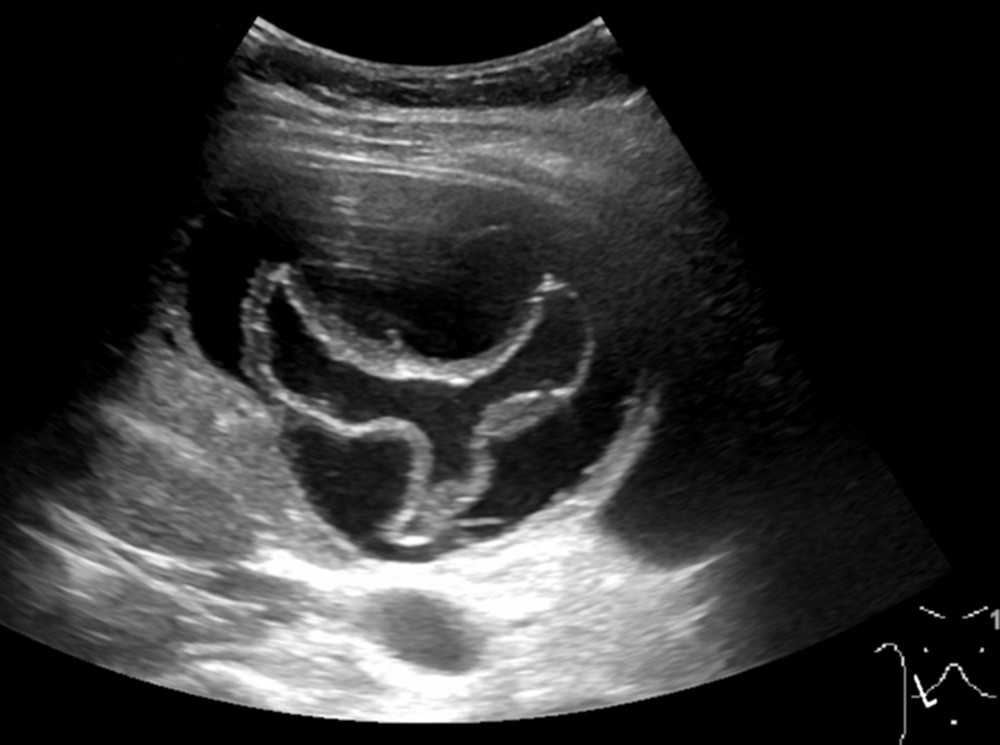

Ultralydundersøkelsen viste en cyste i leveren. Største diameter var 10 cm. Den hadde en foldet indre struktur, forenlig med en separat, flytende indre membran, såkalt vannliljetegn. Dette funnet er karakteristisk for ekinokokkcyste. Pasienten ble henvist videre til infeksjonsmedisiner. Serologiske prøver var også positive for ekinokokker.

Diagnosen stilles på bakgrunn av typiske bildefunn og antistoffundersøkelse. For å avdekke om det foreligger kompliserende forhold (som rumpert cyste eller fisteldanning til galleveiene) bør cysten også utredes med MR- eller CT-undersøkelse (2). Verdens helseorganisasjon (WHO) har utgitt en ultralydbasert klassifikasjon av ekinokokkcyster, og behandlingen bestemmes ut fra WHO-klassifikasjonen og cystens størrelse (2, 3). Behandlingen består enten av observasjon eller medikamentell behandling med albendazol – alene eller i kombinasjon med aspirasjon og reinstallasjon av parasittdrepende middel (f.eks. hypotont saltvann eller etanol) – eller kirurgisk ekstirpasjon av hele cysten.